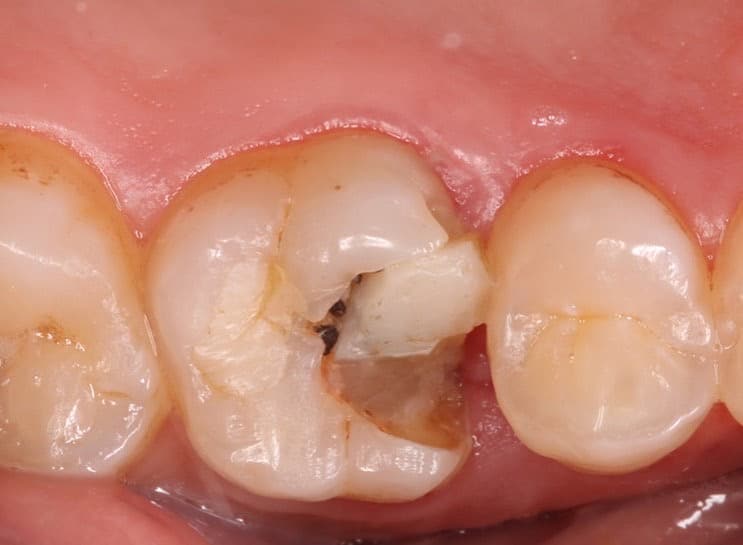

this patient came to my clinic he suffered from bad old composite restoration .

we decided to do in direct emax restoration